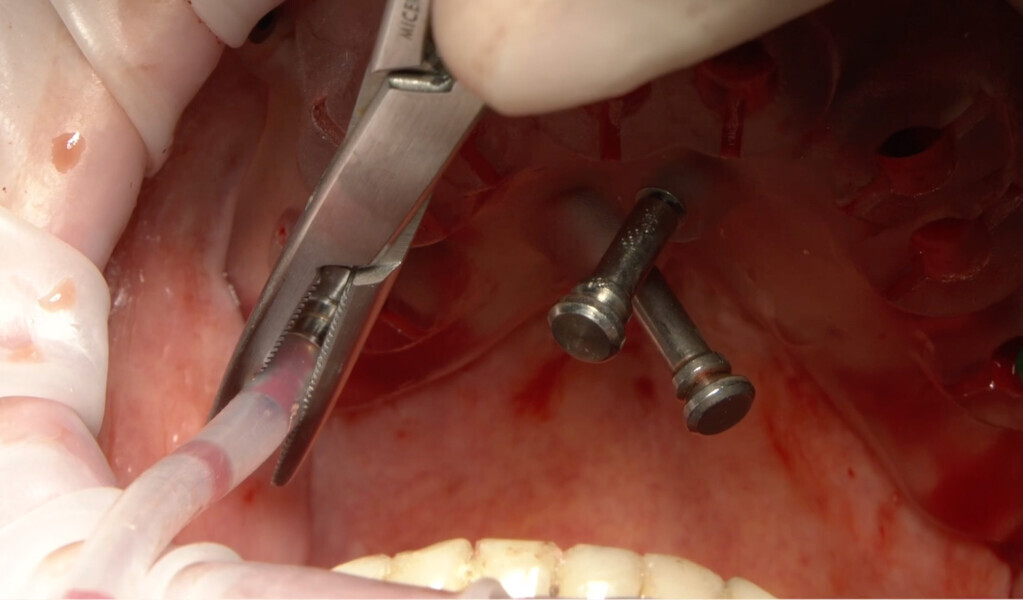

An 85-year-old partially edentulous patient was referred to our clinic for full-arch rehabilitation of the maxilla. The patient was in good general health and a non-smoker. His primary complaints included difficulty in chewing, maxillary pain and occasional halitosis. Clinical and radiographic evaluation revealed a short-span fixed metal–ceramic prosthesis supported by seven anterior maxillary teeth. The prosthesis had debonded, and four of the abutment teeth were structurally compromised. The remaining three showed varying degrees of caries and periodontal problems. A diagnosis of failing dentition was established (Figs. 1 & 2).

On the day of surgery, local anaesthesia was administered, and the first surgical guide was stabilised on the remaining teeth to prepare five anchor pin sites. The compromised teeth were then extracted, and a second surgical guide was secured at the prepared pin sites. Eight implants (Osstem TSIII SOI, Osstem Implant) were placed, five in immediate post-extraction sites and three in previously healed areas. All the placements were fully guided using a surgical guide without metallic sleeves and a dedicated surgical kit (OneGuide KIT, Osstem Implant; Fig. 8).11 One implant required a crestal sinus lift, which was performed using a fully guided approach (OneCAS KIT, Osstem Implant; Fig. 9). Xenograft bone material (A-Oss, Osstem Implant) was used to fill the extraction sockets and the sinus cavity.12 Multi-unit abutments and temporary abutments (Osstem Implant) were immediately placed on all the implants, according to the one abutment, one time concept.13 A prefabricated PMMA-based temporary prosthesis with metal reinforcement was delivered and immediately fixed in the mouth. Chairside adjustments were made to refine the prosthesis and ensure proper occlusion (Figs. 10–12). The patient received postoperative instructions and medication.